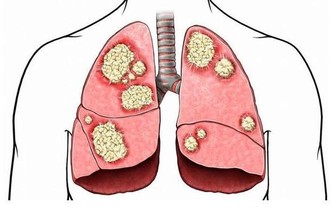

肺:怕煙

除了吸煙、被動吸煙外,廚房油煙、裝修污染等室內環境污染,也是引發肺癌的危險因素。研究表明,廚房通風不良相比通風良好者,患肺癌風險增加了49%。